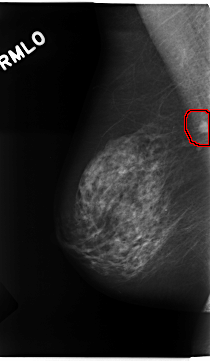

C_0224_1.RIGHT_MLO

RIGHT_MLO LINES 4688 PIXELS_PER_LINE 2728 BITS_PER_PIXEL 12 RESOLUTION 50 OVERLAY

FILE: C_0224_1.RIGHT_MLO.OVERLAY

TOTAL_ABNORMALITIES 1

ABNORMALITY 1

LESION_TYPE MASS SHAPE ROUND MARGINS MICROLOBULATED

ASSESSMENT 5

SUBTLETY 5

PATHOLOGY MALIGNANT

TOTAL_OUTLINES 1

BOUNDARY